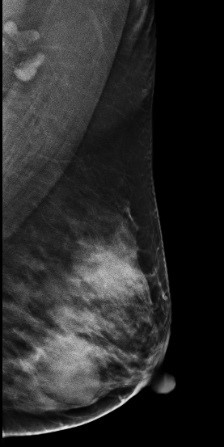

病例4 患者,36岁,常规检查,发现可疑,进一步检查。 2D图像:

影像描述: 常规2D图像MLO位左乳腺内见多个小结节影,下象限似见一团块影,边界模糊,CC位上并没有发现异常团块影,在V-Perview图像MLO位下象限见一类圆形团块影,部分边界尚清,但CC位上并没发现明显异常团块影,DBT断层图像在MLO和CC位上左乳内下象限清晰可见类圆形致密影,其边缘光滑锐利。 影像诊断: 左侧乳腺多发良性结节,BI-RADS 3。 病例点评: 最后病理证实纤维腺瘤,类似这样病例DBT可以给我们提供更多诊断信息有助于明确病变性质。